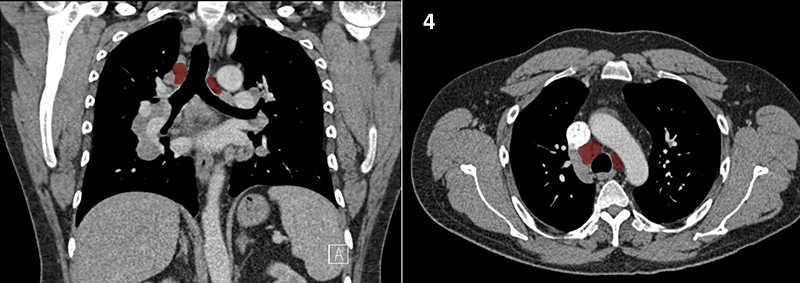

Nodal zones and stations according to the International Association for the Study of Lung Cancer (IASLC) node map.

Table (above): Nodal zones and stations according to the International Association for the Study of Lung Cancer (IASLC) node map. (Source: 1,2) *Depends on the side of the tumour.